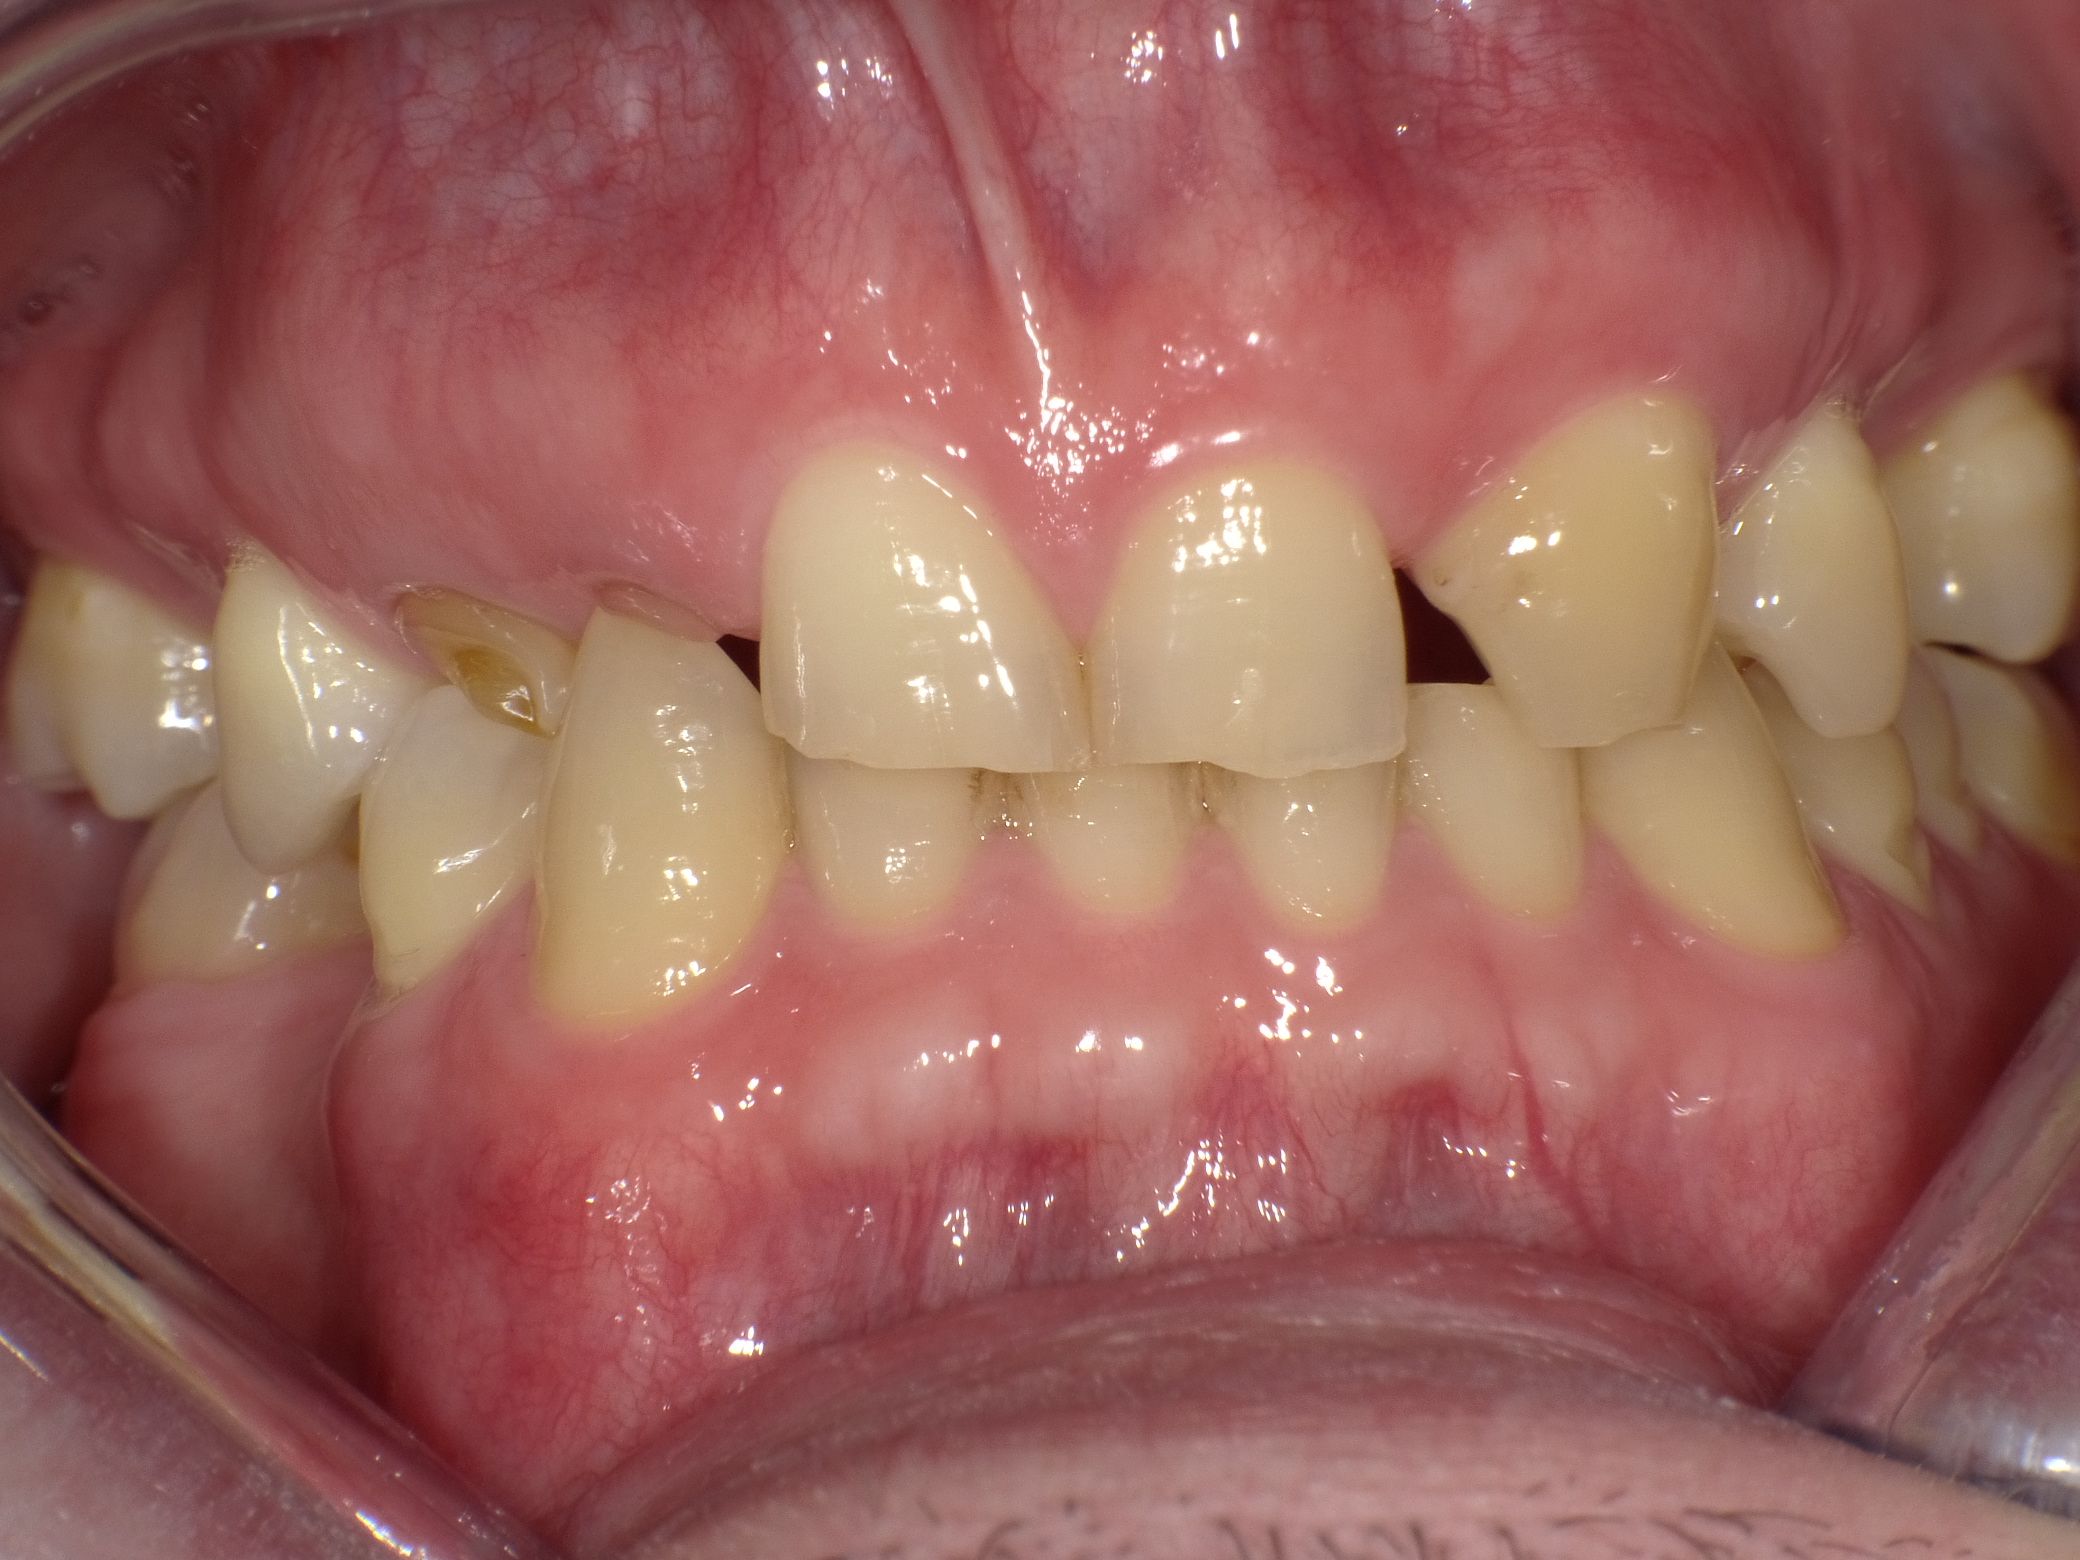

Zahnfehlstellungen und teilweise nicht mehr erhaltungsfähige Zähne durch immer wieder durchgeführte Reparaturen ohne Konzept nach Kassenrichtlinien

Vorher: Zahnfehlstellungen und teilweise nicht mehr erhaltungsfähige Zähne durch immer wieder durchgeführte Reparaturen ohne Konzept nach Kassenrichtlinien

Idealisierung im Rahmen einer Komplettbehandlung mit Vollkeramik; Ersatz der nicht erhaltungsfähigen Zähne durch Implantate

Nachher: Idealisierung im Rahmen einer Komplettbehandlung mit Vollkeramik; Ersatz der nicht erhaltungsfähigen Zähne durch Implantate